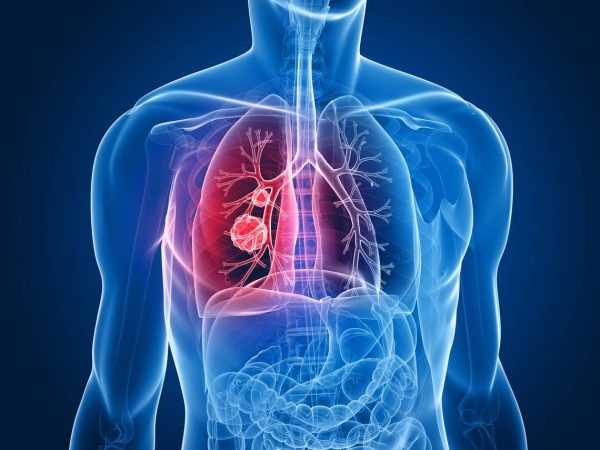

Áp xe phổi do biến chứng viêm phổi

Khi trẻ bị viêm phổi nhưng không được điều trị tốt, gây viêm mủ và hoại tử vùng nhu mô phổi bị tổn thương, khiến cơ chế thanh thải bị suy yếu, gây hiện tượng thuyên tắc hoặc vi trùng lan theo đường máu hình thành nên khối áp-xe phổi. Khối áp xe có hình dạng một hang tròn có bờ rõ, thành dày trong phổi, bên trong có chứ dịch mủ.

Khi thăm khám thấy lồng ngực di động giảm, giảm phế âm, gõ đục, ran ẩm và tiếng thổi ống. Chụp X-quang ngực có thể phát hiện một ổ mủ đơn độc, thành dày trong phổi có hoặc không có mức khí dịch.